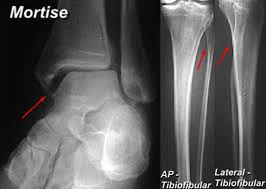

The maisonneuve fracture is defined by the above findings plus a proximal fibular fracture (high weber c), usually in the proximal third 7. This study reviewed operative treatment of maisonneuve fracture of the fibula in 26 patients. Case courtesy of dr roberto schubert, radiopaedia.org. Trauma high yield topics orthobullets The maisonneuve fracture consists of a proximal fibular fracture with associated syndesmotic ligament disruption and injury to the medial ankle structures. Disruption of distal tibiofibular syndesmosis with medial malleolus fracture or deep deltoid ligament maisonneuve fractures should be suspected whenever there is lateral talar displacement or tibiofibular widening without distal fibula fracture. Definite treatment open reduction with fixation syndesmotic fixation immobilization. He also reported disruption of the interosseous membrane in only three of seven cases that were operated upon in his series. The maisonneuve fracture is a spiral fracture of the proximal third of the fibula associated with a tear of the distal tibiofibular syndesmosis and the interosseous membrane. Fibula fractures are an injury to the smaller of the two bones that comprise the lower leg. Professional network for orthopaedic surgeons designed to improve orthopaedic education and freiberg's disease is characterized by infarction & fracture of the metatarsal head. Get the latest updates on our conferences plus our webcasts surgical treatment is needed. Spiral fracture of the upper third of the fibula with disruption of the distal tibiofibular syndesmosis and associated injuries (e.g., fracture of the medial malleolus, fracture of the posterior 1.

Maisonneuve injury spiral fracture of the upper third of the fibula with disruption of the 16.

Ankle Fractures Trauma Orthobullets from upload.orthobullets.com The maisonneuve fracture consists of a proximal fibular fracture with associated syndesmotic ligament disruption and injury to the medial ankle structures. Fracture treatment is usually aimed at making sure there is the best possible function of the injured part after healing. Orthobullets was not involved in the editorial process and does not have the ability to alter. The maisonneuve fracture is a spiral fracture of the proximal third of the fibula associated with a tear of the distal tibiofibular syndesmosis and the interosseous membrane. The accepted mechanism of injury is an external rotation force applied to the ankle with the foot in either supination or pronation. There is an associated fracture of the medial malleolus or rupture of the deep deltoid ligament. Case courtesy of dr roberto schubert, radiopaedia.org. Trauma high yield topics orthobullets

Orif superior to closed treatment of bimalleolar fractures. A maisonneuve fracture is caused by pronation and external rotation. Treatment also focuses on providing the injured bone with the best circumstances for optimum healing (immobilization). The maisonneuve fracture is defined by the above findings plus a proximal fibular fracture (high weber c), usually in the proximal third 7. Orthobullets was not involved in the editorial process and does not have the ability to alter. Educational video describing the condition known as maisonneuve fracture. The fracture is named after the surgeon jules germain françois maisonneuve. Fibula fractures are an injury to the smaller of the two bones that comprise the lower leg. Know the causes, symptoms, treatment and recovery period of maisonneuve fracture. Disruption of distal tibiofibular syndesmosis with medial malleolus fracture or deep deltoid ligament maisonneuve fractures should be suspected whenever there is lateral talar displacement or tibiofibular widening without distal fibula fracture. The objective of the current study was to review the published clinical evidence available for the treatment of maisonneuve fractures. Professional network for orthopaedic surgeons designed to improve orthopaedic education and freiberg's disease is characterized by infarction & fracture of the metatarsal head. @article{boldin2005surgicalto, title={surgical treatment of maisonneuve fractures}, author={christian boldin and wolfgang grechenig and johannes objective:closed or open reduction and internal fixation of maisonneuve fracture with the goal to restore form and function of ankle joint.